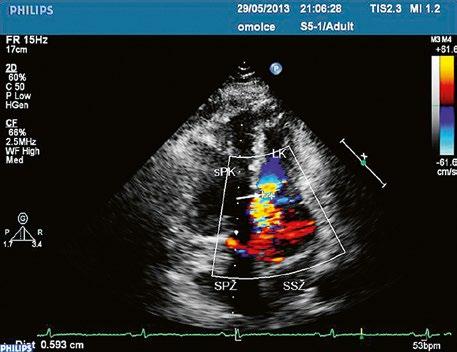

Poslechový nález systolického šelestu nad plicnicí s fixním rozštěpem 2. ozvy je nenápadný. Echokardiograficky je patrná dilatovaná a objemově přetížená pravá komora s paradoxním pohybem septa (Obr. 45.9), zkratový tok může být vidět i transtorakálně (TTE) (Obr. 45.10, Video 45.3, Video 45.7), ale suverénní diagnostickou metodou je jícnová echokardiografie (TEE), případně s 3DE zobrazením (Obr. 45.1, Obr. 45.2,

Obr. 45.10 TTE, čtyřdutinová apikální projekce s levo pravým zkratem na úrovni síní (šipka) při defektu septa síní typu secundum PK – pravá komora, LK – levá komora, LS – levá síň, PS – pravá síň